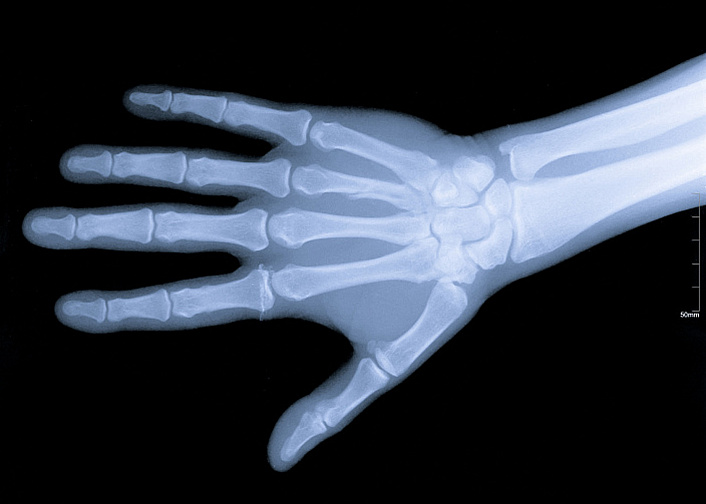

Анатомия кисти руки человека довольно сложна. Поскольку это очень подвижная часть тела, в ней множество костей и суставов, связок и мышц, также человеческие пальцы, в отличие от конечностей животных, имеют ногти. Кожа рук также отличается от кожного покрова тела, имея специфические складки и особую чувствительность. Итак, начнём с обзора костей. Кости кисти делятся на три отдела: запястье, включающее восемь костей; пясть, состоящая из пяти длинных костей, и пальцы, насчитывающие в общей сумме четырнадцать фаланг. Фаланги относятся к трубчатым костям, в отличие от остальных костей, составляющих кисть. Все кости довольно мелкие и расположены друг к другу очень близко.

Благодаря тому, что костей много и они небольшие, кисть имеет такую пластичность и подвижность, однако из-за этого при травмах работоспособность кисти заметно снижается. Кости запястья образуют как малоподвижные соединения (например, в области запястья), так и суставы. Лучезапястное соединение имеет форму полукруга и обеспечивает сгибание и разгибание кисти. Это очень сложный сустав, дающий кисти широкий диапазон движений. Кости запястья соединены между собой связками и образуют прочное сочленение, способное выдерживать большие нагрузки при опоре на кисть. У основания большого пальца расположен седловидный сустав, позволяющий совершать движения в двух осях, что делает большой палец очень функциональным.

Кости фаланг имеют шаровидные соединения, что позволяет пальцам сгибаться только в одной плоскости. Из-за этого пальцы весьма подвержены травмам. В отличие от остальных пальцев, насчитывающих по три фаланги, большой палец короче и состоит всего из двух костей. Кисть имеет широкую сеть инервации, отвечающую за осязание, движение, работу сальных и потовых желёз и терморегуляцию. Вообще руки тесно связаны с психическим состоянием человека. В моменты стресса руки часто трясутся, немеют, из них всё валится, человек утрачивает способность владеть ими в полной мере. Также при эмоциональных всплесках ладони могут похолодеть или вспотеть.